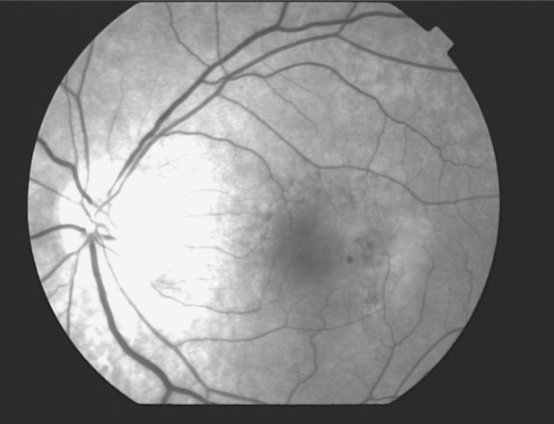

geographic or central areolar RPE atrophy

a form of dry AMD consisting of large areas of GA of the RPE

histologic: the area of GA is associated w/ focal loss of the retinal receptor cells, RPE, & choriocapillaris

5-10% of pts w/ AMD lose central vision as a result of this form of AMD

one or more sharply circumscribed geographic areas of atrophy of the RPE & retinal in the posterior pole

central vision is slow & progressive as the atrophic concentric area enlarges

bilateral, symmetric

20% of these pts will develop CNVM in the 2nd eye

FA shows varying degrees of loss of the choriocapillaris w/in the area of GA

GA

GA

GA

GA

GA